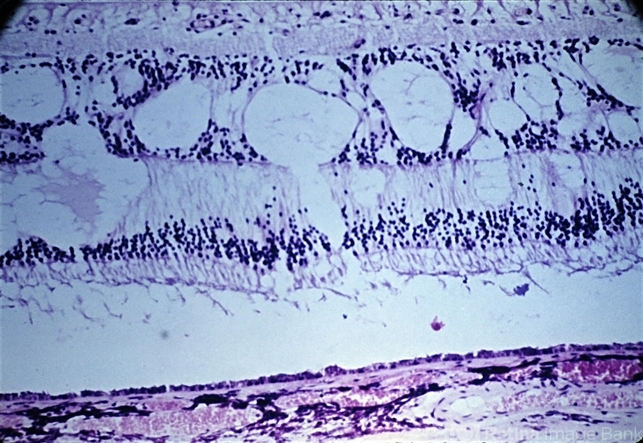

- retinal edema

- Retinal edema. The retina is thickened by a lightly staining proteinaceous material that accumulates principally in the inner nuclear and outer plexiform layers.